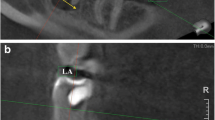

Measurement of the angle formed by the axis of the basal bone triangle with the axis of the tooth in the upper and lower arches (Fig. 3).

The angle of the basal bone triangle was defined by two reference points in the palatal and vestibular areas at the apex and other two points in the apical part of the basal bone triangle. A perpendicular line passes across these horizontal lines at the middle. With the angle tool, the axis of the tooth and the axis of the basal bone were drawn, and the angle formed in their intersection was determined.

The angulation between the axis of the teeth and the alveolar process

In the maxilla, only 31 of 66 incisors, 6 of 32 canines, 18 of 47 premolars and 32 of 58 M had an angle less than 10°. In the mandible, the maximum angulation was found in some molars (43.26°) and incisors (38°) (Table 4, Figs. 4, 5).

In relation to the angle of the root axis and basal bone axis, our research found that in the upper jaw, the mean values were as follows: 11.67 ± 6.37° for incisors, 16.88 ± 7.93° for canines, 13.93 ± 8.6° for premolars, and 9.89° ± 4.8° for molars. In the mandible, the mean values were 10.63 ± 8.76° for incisors, 10.98 ± 7.36° for canines, 10.54 ± 5.82° for premolars and 16.19 ± 11.22° for molars. However, a maximum of 43.26° was found in some molars and 38° in some incisors.

According to Nishihara et al., the mean value of the angle of maxillary first premolars was 25.5° and 18.1° for second premolars. The insertion angle of the dental implant may leave a depression in the buccal bone that could induce implant protrusion to the vestibular bone in longer implants [35].

According to Kan et al. (2011), the class I type, in which the root is closer to vestibular wall, represents 81.1% of the cases. These angulations are in most cases greater than 10° from canine to canine. The sagittal position of the tooth in the alveolar bone is important for the clinician to make decisions for implant-based therapy [11].

In 2014, Wang found differences greater than 10° in all groups, even up to 42° in some premolars and upper canines. These differences in the results of angulation were greater than 20° in 50% of anterior teeth (and 40% of the canines > 30°). This could be a consequence of the patient’s skeletal class [36]. In this study, the sagittal angle formed between the long axis of the tooth and the long axis of the alveolar bone was < 10° degrees at only 10% of the teeth in the maxillary aesthetic zone.

In more recent studies, the angulation of the tooth axis is related to the horizontal plane and the buccal bone wall. The more obtuse the angle, the thinner the buccal wall. This situation implies increased risk of perforation of the buccal wall in immediate implant placement [31]. In our opinion, the clinical relevance of these data is that in cases where immediate implants are placed according to bone availability, angulated screwed abutments may be required. In some cases, such as premolars and canines, this might require CAD/CAM-customized components, since available standard angulated screwed abutments are not able to compensate for the resulting discrepancy between angulations. Nevertheless, in the mandible, 8% of incisors and 27% of second molars seem to have angulations bigger than 30° between the basal bone and dental alveolus.